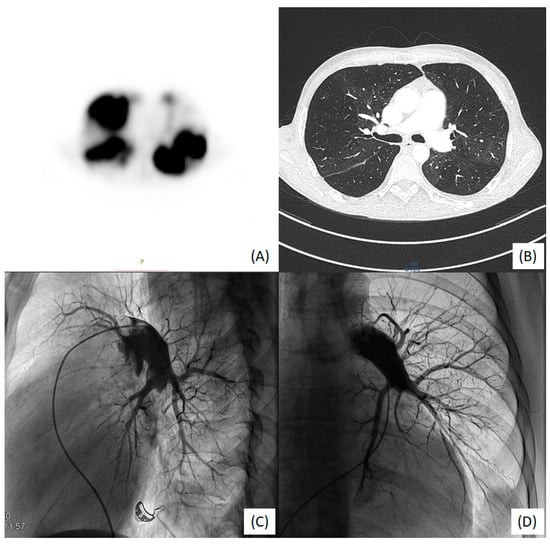

2. Case Presentation